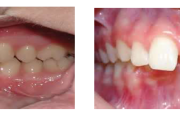

Ravijärgne seis. Jäävhammas on täielikult lõikunud.

Normaalse jäävhammaskonna pilt küljelt ja eest vaadatuna.